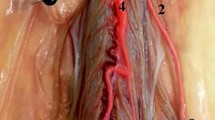

The artery of Adamkiewicz (AKA), also known as the great anterior radiculomedullary artery, is a major artery that joins the anterior spinal artery in the lower one-third of the spinal cord (Fig. 1) [1]. Because of its large role in feeding the spinal cord, many reports have stressed the importance of reattaching the intercostal or lumbar arteries to the AKA in the event of spinal cord ischemia following vascular and endovascular surgery (Fig. 2). Identification of the AKA preoperatively helps surgeons to determine the appropriate range of aortic lesions that require graft replacement [2]. Therefore, accurate localization and detailed anatomical knowledge of the AKA are important when planning surgical and interventional radiological treatments of thoracoabdominal diseases and spinal lesions in order to help reduce the risk of postoperative ischemic spinal complications and paraplegia.

The AKA is the most dominant anterior radiculomedullary artery and is responsible for the arterial blood supply to the spinal cord from T8 to the conus medullaris [3]. Its origin is highly variable and extends from the mid-thoracic level to the lumbar levels, including the bilateral T3-T12 intercostal arteries [4] and L1-L4 lumbar arteries [5]. It typically arises from the T8–L1 neural foramina [6] from the left intercostal or lumbar arteries [7]. The AKA has a diameter of 0.8–1.3 mm, and the distal portion of this artery, together with the anterior spinal artery, forms a characteristic “hairpin” turn [8] (Fig. 3). Various techniques have been devised to preoperatively identify the location and anatomy of this artery. Such techniques include computed tomography angiography (CTA), magnetic resonance angiography (MRA), and digital subtraction angiography (DSA), with the latter considered the gold standard [9].